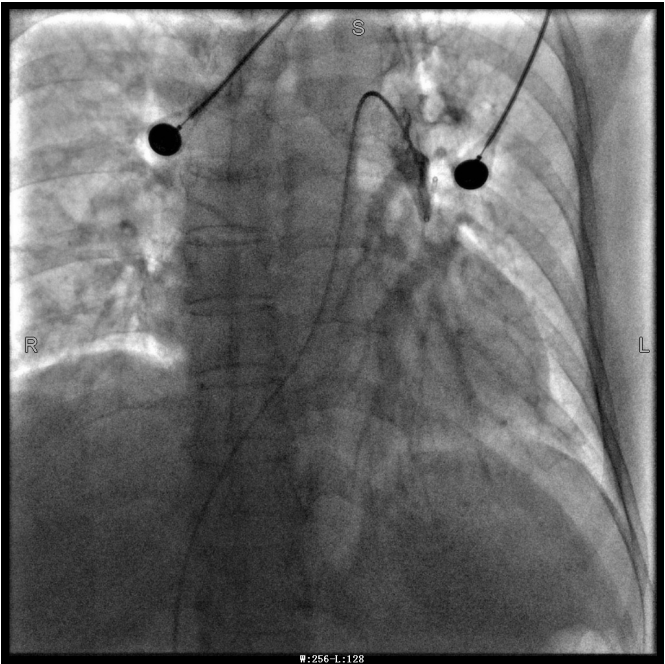

譚婆婆今年已經(jīng)72歲了,因“突發(fā)意識障礙2次”到璧山區(qū)人民醫(yī)院神經(jīng)內科治療。譚婆婆沒有基礎心臟病病史,但近段時間活動耐量明顯下降,稍做活動就出現(xiàn)呼吸困難。入院后查BNP及心臟彩超均未提示明顯異常,查D二聚體明顯升高,經(jīng)心血管內科周波醫(yī)師會診后轉入科室繼續(xù)治療。在心血管內科主任、內科學(心血管病)博士于長青的指導下,周波醫(yī)師成功完成醫(yī)院首例“一站式”微創(chuàng)介入手術。在影像中,可以清晰地看到堵塞的血管經(jīng)溶栓治療后,重新暢通無阻,流動起支撐生命的血液。

第三章未標注圖像為術后圖像